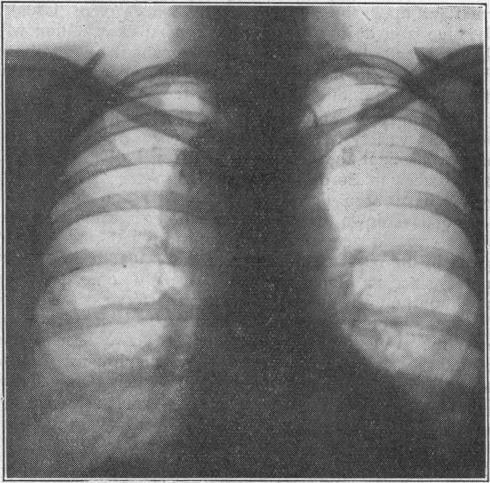

Thyroid Surgery, with a Contribution on Intrathoracic Goitre.

Br Med J. 1950 Mar 18;1(4654):621-6. doi: 10.1136/bmj.1.4654.621.